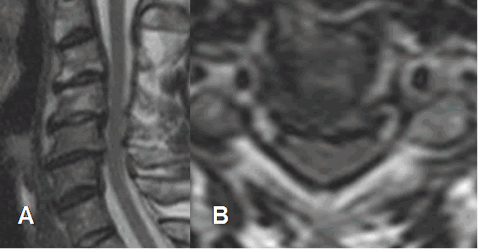

Fig 50. Acondroplasia.

A: RM axial y B: RM sagital en T2. Disminución en la amplitud del canal de origen congénito, con discos, ligamentos y facetas articulares normales.